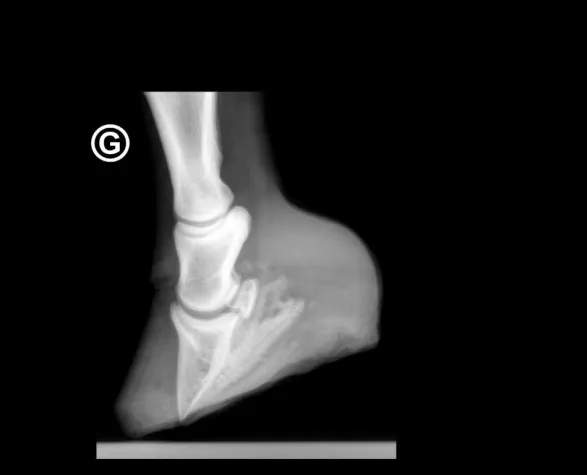

Wir möchten Ihnen noch aufzeigen, was mit dieser Methode gemacht werden kann. Das obenstehende Röntgenbild zeigt die Situation einer Schweizer Warmblutstute mit einem 14-tägigen Fohlen bei Fuss. Aus Sicht mehrerer Mediziner war die Stute verloren, da sie kurz vor einem Hufbeindurchbruch stand. Zudem begann von der Mitte her der Kronrand aufzuplatzen, was im Normalfalle auf das „Ausschuhen“ eines Hufrehepferdes hindeutet.

Nur in einer aufwendigen „Kühlaktion“ - über 14 Tage - konnte die Stute gerettet werden. Sie ist, zusammen mit ihrem Fohlen wohlauf und bewegt sich mit Hufschuhen einwandfrei. Wir sind uns bewusst, dass das Anbringen von Eiswürfeln jede Stunde – besonders Nachts – ein grosses Engagement erfordert. Der Erfolg wird jedoch für alle Beteiligten die schönste Belohnung sein!